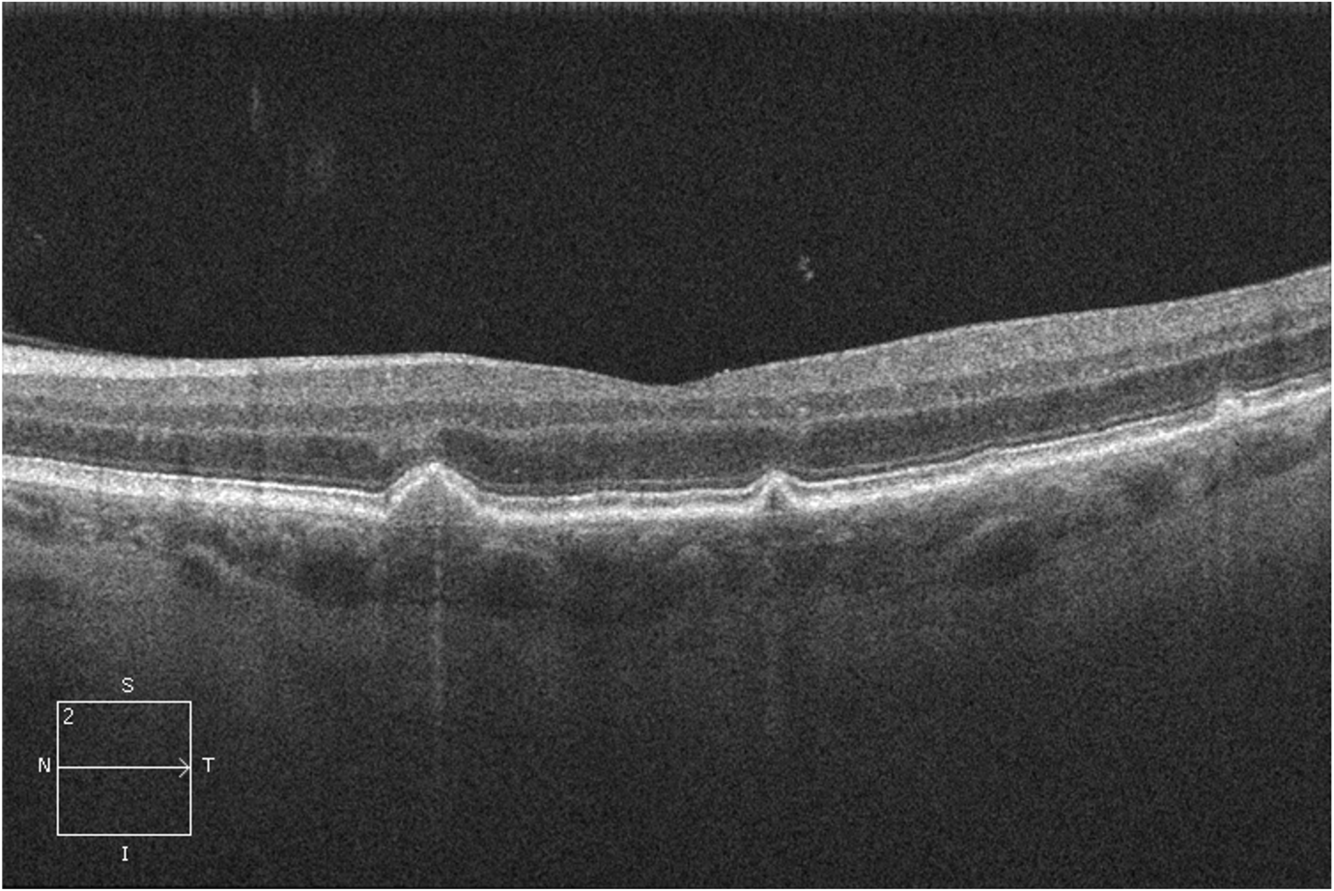

12

Drusen AMD OCT